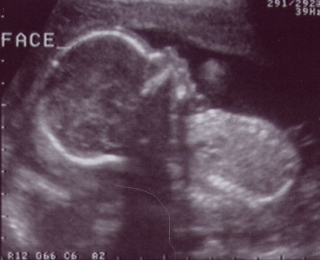

Here's my first picture. The technician is estimating that I am 8 weeks along at this point. I'm pretty small, but I'm growing fast. |  This is me at 12 weeks. Now you can see some of my body parts. It looks like I'm upside down because I am facing Mommy's back. I was too camera shy to turn around. I am just over 6 cm long -I still have a lot of growing to do to catch up to my big sister. |